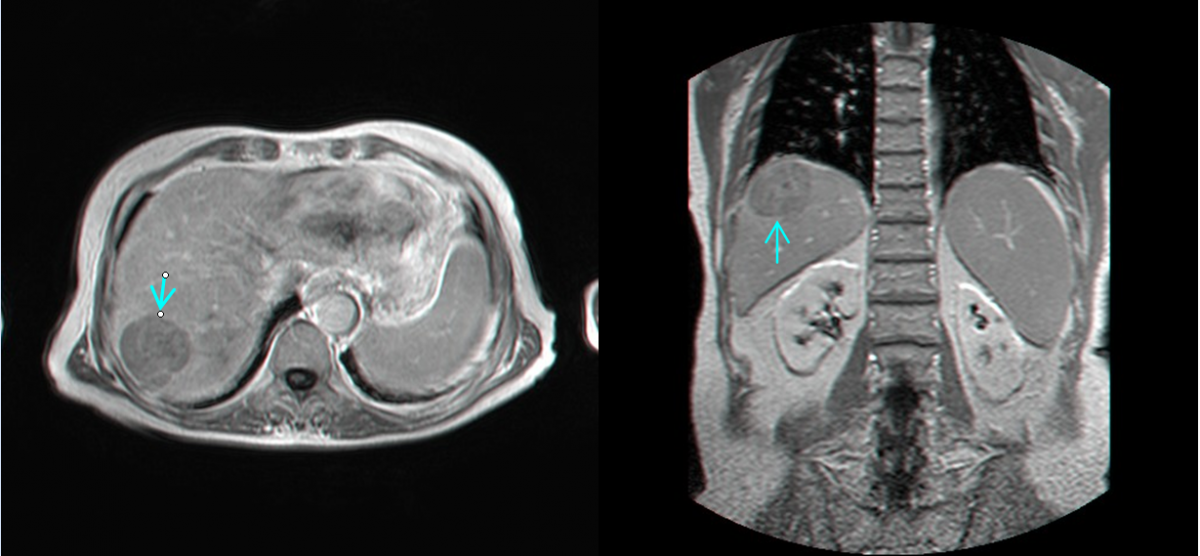

U gan ác tính: Hiểu đúng để phát hiện sớm và điều trị kịp thời

U gan ác tính là khối u xuất hiện trong nhu mô gan do tế bào gan tăng sinh bất thường hoặc do tế bào ung thư từ cơ quan khác di căn. Bệnh thường khó nhận biết khi còn ở giai đoạn đầu.

4. Chẩn đoán

CT, MRI đánh giá mức độ xâm lấn.